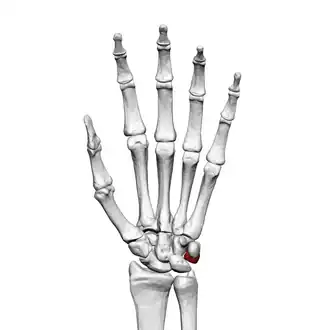

Left hand anterior view (palmar view). Triquetral bone shown in red.

The triquetral bone (/trˈkwɛtrəl, -ˈkw-/; also called triquetrum, pyramidal, three-faced, and formerly cuneiform bone) is located in the wrist on the medial side of the proximal row of the carpus between the lunate and pisiform bones. It is on the ulnar side of the hand, but does not directly articulate with the ulna. Instead, it is connected to and articulates with the ulna through the Triangular fibrocartilage disc[1] and ligament, which forms part of the ulnocarpal joint capsule.[2] It connects with the pisiform, hamate, and lunate bones. It is the 2nd most commonly fractured carpal bone.

The triquetral is one of the eight carpal bones of the hand. It is a three-faced bone found within the proximal row of carpal bones. Situated beneath the pisiform, it is one of the carpal bones that form the carpal arch, within which lies the carpal tunnel. [3]: 708

The triquetral bone may be distinguished by its pyramidal shape, and by an oval isolated facet for articulation with the pisiform bone. It is situated at the upper and ulnar side of the carpus. To facilitate its palpation in an exam, the hand must be radially deviated so that the triquetrium moves out from under the ulnar styloid process. The triquetrum may be difficult to find, since it also lies under the pisiform.